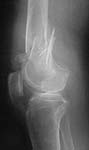

Please see attached pics of an 82 yo woman who lives independently and is a community ambulator s/p low energy fall w/ SC femur fx below a stable uncemented THA (1990).

Looks like SupraCondylar, and IntraCondylar involvements.